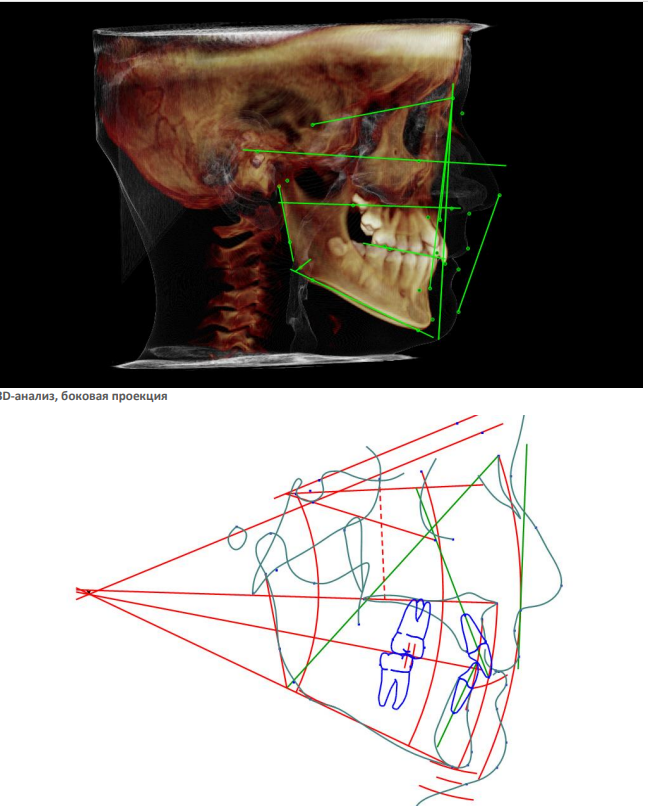

На КЛКТ определяются зачатки вторых и третьих моляров на верхней и нижней челюсти, степень формирования которых соответствует возрасту и полу. Невысокое положение клыков с увеличенной мезиальной ангуляцией.

На ТРГ головы в боковой проекции - ретроположение верхней и нижней челюсти в сагиттальном направлении без нарушения размеров апикальных базисов и их взаиморасположения. Тип роста – нейтральный. Дентоальвеолярный анализ характеризует изменение инклинации резцов на верхней и нижней челюсти с незначительным дентоальвеолярным удлинением. На нижней челюсти в области боковой группы зубов определяется зубоальвеолярное укорочение, что характеризует формирование глубокой кривой Spee на данном этапе формирования прикуса постоянных зубов. (рис.3.)

Рис. 3. КЛКТ и ТРГ головы в боковой проекции пациента А. до лечения.